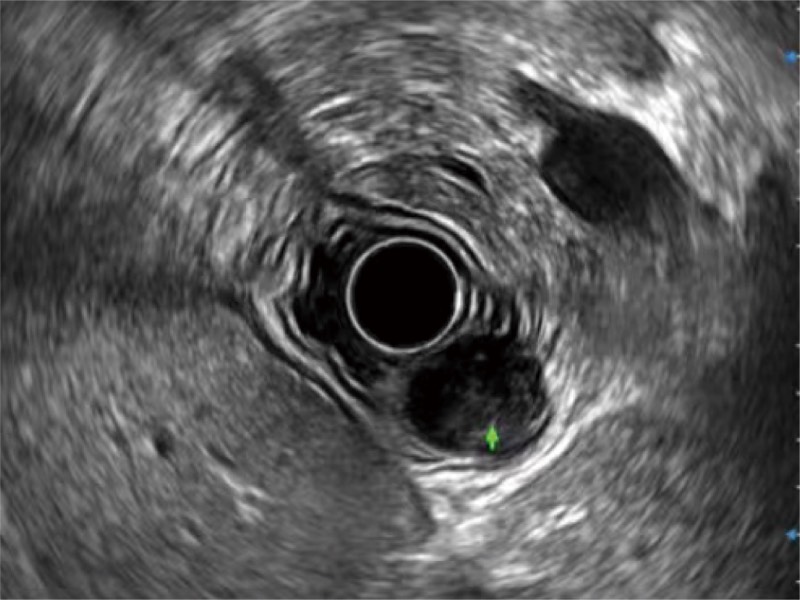

食管内间质瘤清晰显像

卓越的宽频设计,满足医生探查不同深度的组织和器官